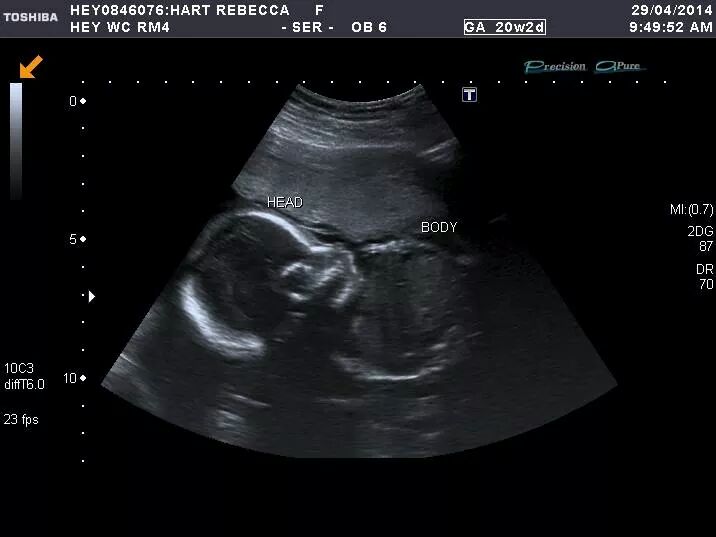

Attachment 18570 Hi All! Please see pic of my baby's ultrasound at 20+2 weeks. Sonographer was unable to confirm sex as baby was sat cross-legged and have to return for another scan. Any guesses on the gender using skull theories? (no nub in view!) Its BPM was 141 at 16 weeks which may suggest boy, but Sonographer said it MAY be a girl! Guesses very much appreciated, thank you, :)